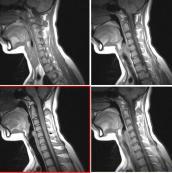

視神經脊髓炎(NOM)是視神經與脊髓同時或相繼受累的急性或亞急性脫髓鞘病變,又稱Devic病或Devic綜合癥,其臨床特征為急性或亞急性起病的,單眼或雙眼失明,其前或其后數周伴發橫貫性或上升性脊髓炎。